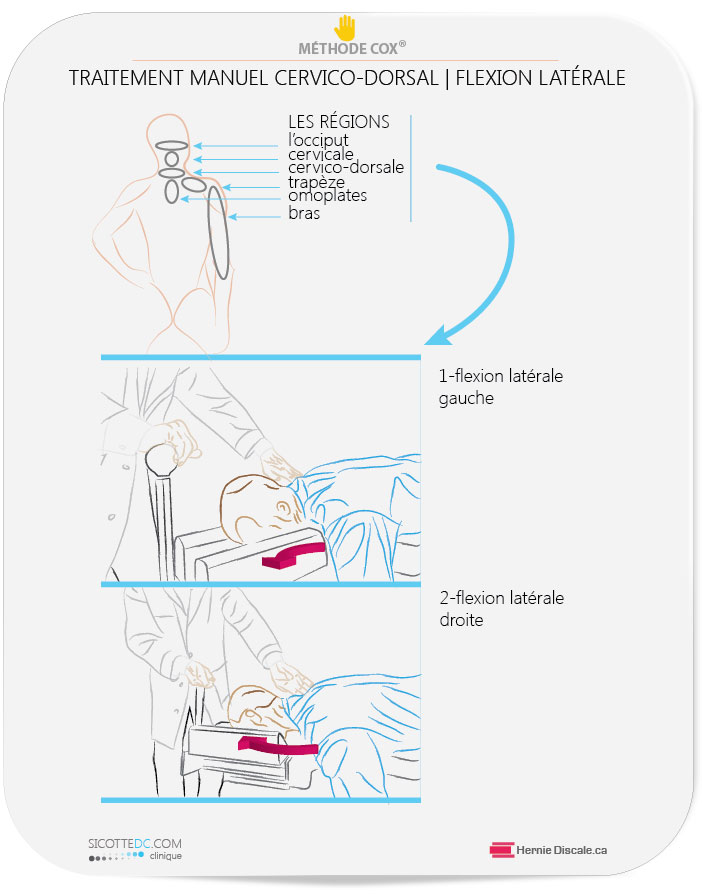

Les objectifs du traitement pour arthrose cervicale (sans manifestation neurologique), dans l’exemple qui suit, sont :

de redonner délicatement au patient une certaine extension au cou d’induire délicatement une certaine rotation du cou .

Les manœuvres sont exécutées avec douceur et dans le respect des limites physiologiques. La méthode Cox® fait l’objet de nombreuses recherches en laboratoire pour le compte du NIH (National Institute of Health) américain.

L’EXTENSION CERVICALE ET LA MÉTHODE COX® | TRAITEMENT

L’arthrose cervicale a pour effet de diminuer l’extension cervicale (la tête vers l’arrière). Chez les patients qui ne manifestent pas de signe neurologique, la première étape est d’améliorer l’extension cervicale. Le mouvement de la tête vers l’arrière est essentiel.

Après l’historique, l’examen physique et la radiographie, le clinicien applique l’extension nécessaire adéquate afin de faire cheminer le patient vers une amélioration de son état.

L’augmentation de l’amplitude de mouvement inhibe la douleur chez les patients qui souffrent d’arthrose cervicale. La méthode est extrêmement douce et sans mouvements rapides.

Le traitement des douleurs au cou est unique : contrairement à la région du milieu du dos, le cou est très mobile et fragile. En clinique, une méthode très spécifique est utilisée pour soigner le cou.

Traitement : Les soins seront des manipulations et des flexions-distractions Cox®appliquées à la région cervico-dorsale.